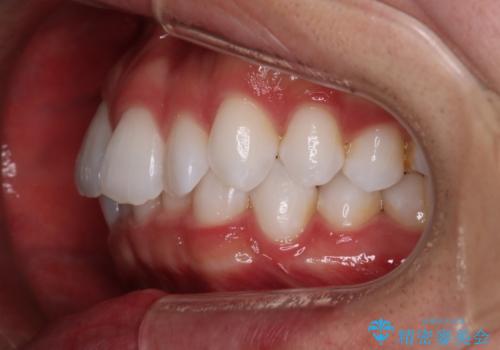

治療症例の内容

- 患者様

- 20代男性

- 矯正装置

- インビザライン

- 治療期間

- 1年

- 治療回数

- 5-10回

- 治療計画

- がたつきが気になるとの事で来院されました。

目立たない装置で費用も抑えたいとの希望があったため、インビザラインにて治療をすることとなりました。

上下顎ともにIPR(歯と歯の間を削る処置)を行い歯並びを整える治療計画を立てました。

治療当初は、計画通りに治療が進むか心配でしたが、しっかりマウスピースを使用していただいたことで

治療期間も長引くことなく歯並びを綺麗に改善することが出来ました。

患者様の希望もあり、前歯の微調整で1回リファイメント(マウスピースの再発注)を行いました。

患者様の希望に沿う治療を提案することができ良かったと思います。